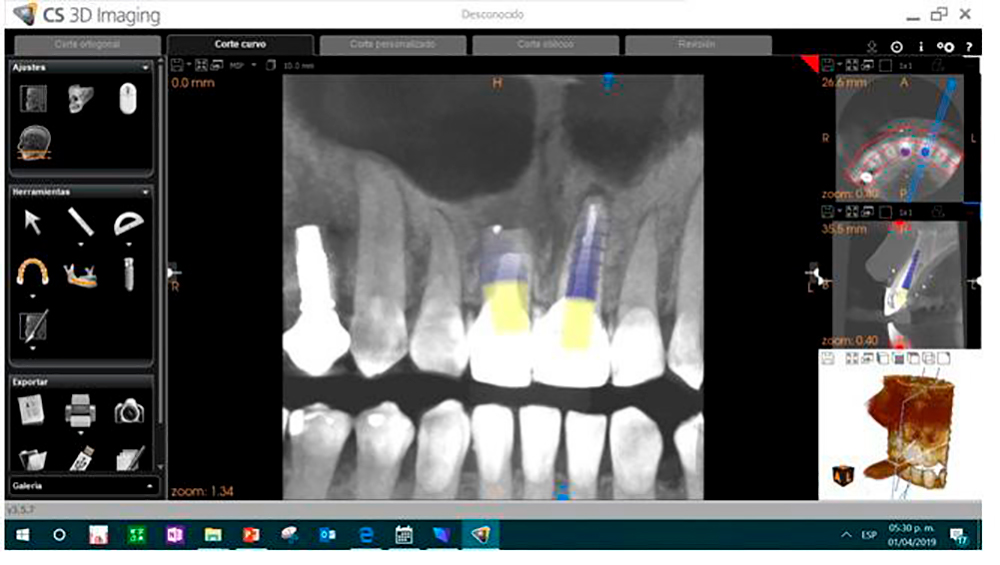

• Implantación con Guía por Mapeo Tomográfico

Socket preparation prior implant placement Using DSI DNT Drills